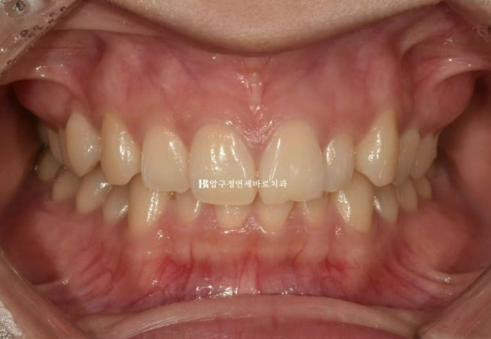

덧니와 왜소치, 과개교합, 중심선 불일치 등 문제가 복잡해보이지만, 앞니 부분교정으로 단기간에 어떤 결과까지 가능한지 보여드리겠습니다.

송곳니 덧니 등 앞니를 가지런하게 만들고 싶어 내원하신 분 입니다.

결혼을 앞두고 계셔서 전체교정은 부담스럽다 하셨고 최소한의 개입만으로 단기교정치료를 원하셨습니다.

다행히 어금니 교합이 양호한 편이고 앞니 부분교정도 권유드렸습니다.

앞니 부분교정만으로도 전체교정 못지 않은 좋은 결과를 얻을 수 있을 때에만 앞니 부분교정을 권유드립니다.